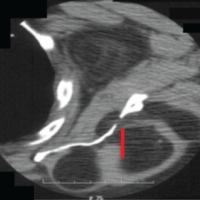

Within this context, two diagnostic corticosteroid injections of the compromised segment were performed with favorable, yet transient, responses. Owing to pain persistence and functional limitations, surgical resection of the transverse process was suggested. Surgery was performed through the Wiltse posterolateral approach at the right lumbosacral level. Fluoroscopic guidance was used to localize the transverse-sacral pseudoarticulation (Fig. 5) and to define the anatomical limits of the mega-transverse process.

Figure 5: An intraoperative fluoroscopic image. (a) Preop and (b) postop with resection of the transverse-sacral pseudoarticulation (arrow) are shown.